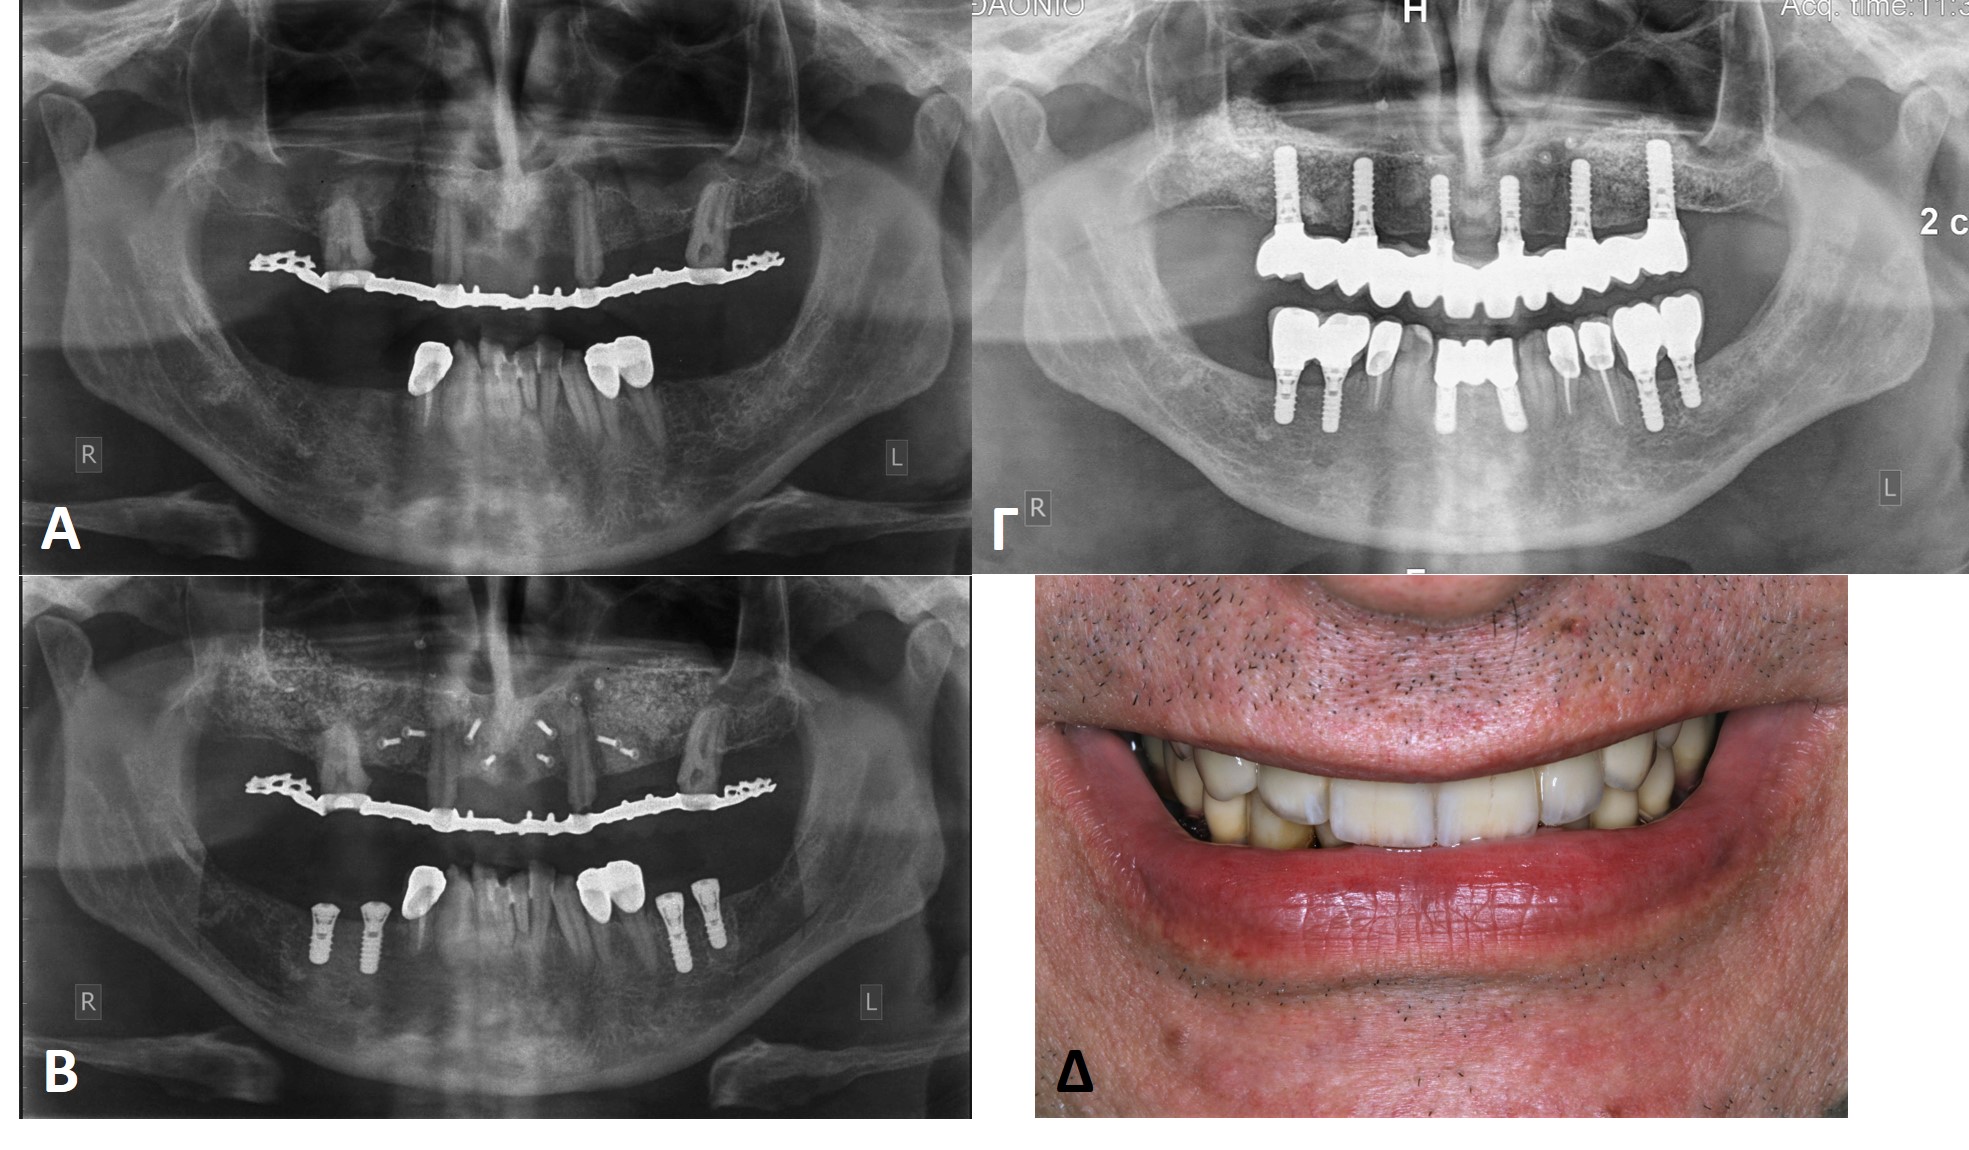

3)       Η ανάπλαση της ελλειμματικής φατνιακής ακρολοφίας της άνω ή της κάτω γνάθου με block αυτογενούς οστικού μοσχεύματος (autogenous block graft) από ενδοστοματική δότρια θέση (γενειακή σύμφυση ή κλάδος της κάτω γνάθου). Σε τέτοιες περιπτώσεις τα αυτογενή οστικά blocks ακινητοποιούνται επί των δεκτριών θέσεών τους με micro βίδες οστεοσύνθεσης. Σε δεύτερο χρόνο προγραμματίζεται η επανείσοδος στην αναπλασμένη πλέον περιοχή για την αφαίρεση των βιδών οστεοσύνθεσης και την τοποθέτηση των οδοντικών εμφυτευμάτων (Εικόνα 15).

4)       Σε εκτεταμένα ελλείμματα της άνω και της κάτω γνάθου η αποκατάσταση κατά πάχος και καθ’ ύψος της ατροφικής γνάθου μπορεί να γίνει με τη βοήθεια πλέγματος τιτανίου (titanium mesh 3D augmentation), εντός του οποίου στοιβάζεται κοκκώδες αυτομόσχευμα από ενδοστοματική ή εξωστοματική δότρια θέση. Το πλέγμα ακινητοποιείται σταθερά με micro βίδες οστεοσύνθεσης και η επανείσοδος για την αφαίρεση αυτών των υλικών και την τοποθέτηση οδοντικών εμφυτευμάτων προγραμματίζεται να γίνει μετά από 4 ως 6 μήνες (Εικόνα 16).